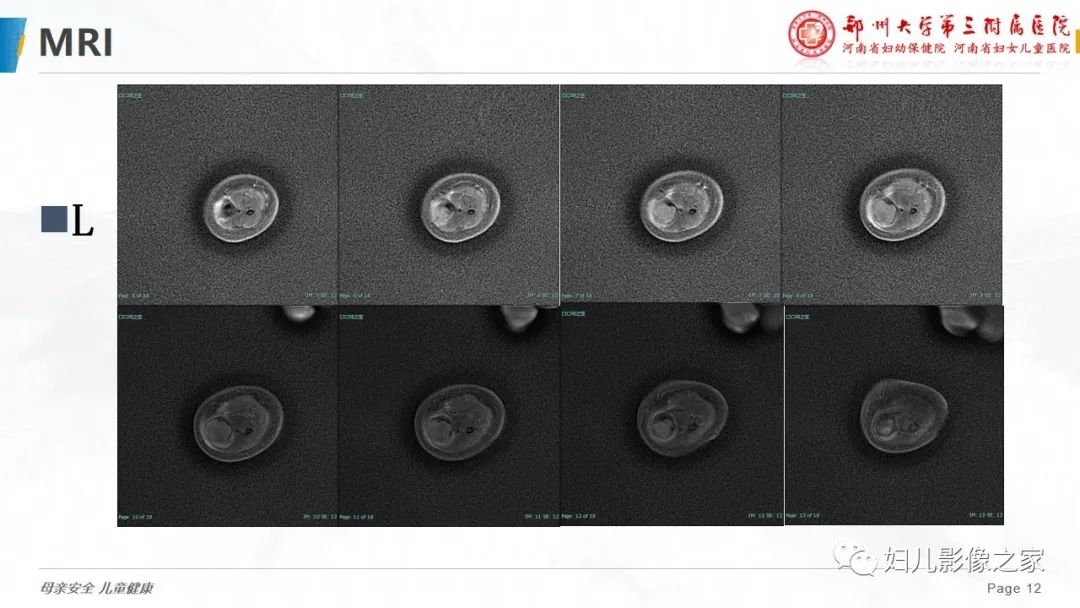

【PPT】骨纤维结构不良-12